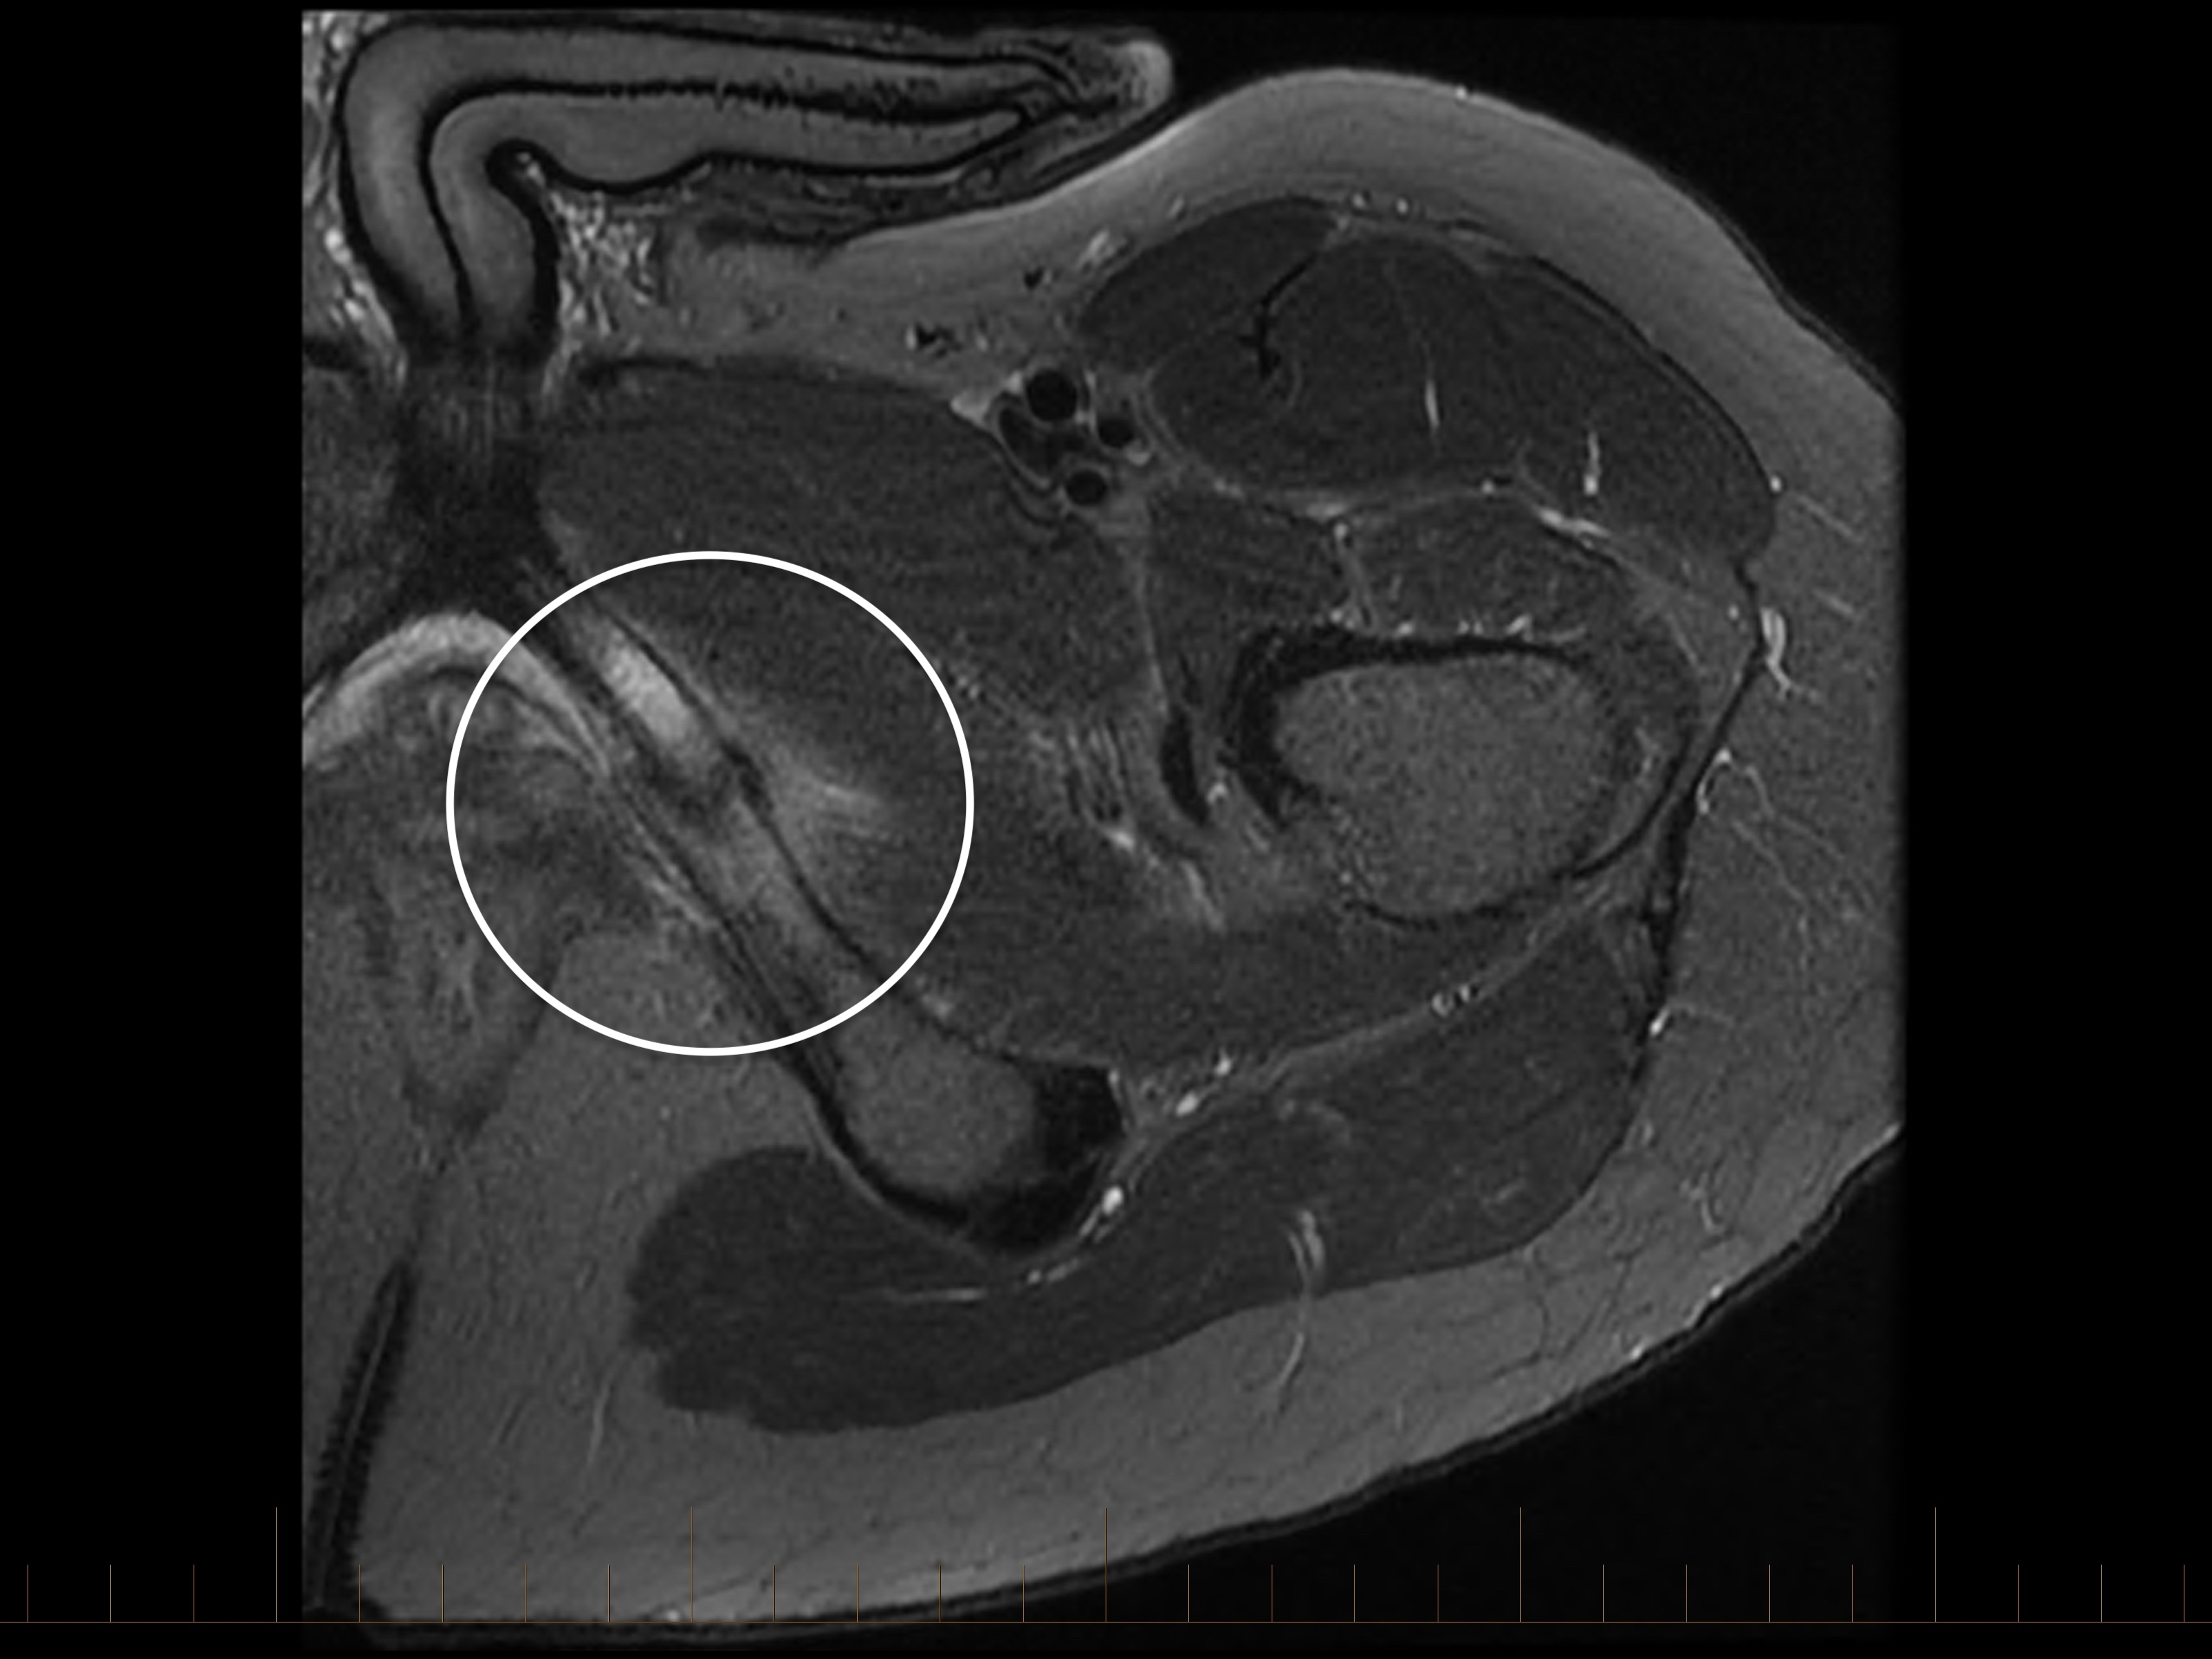

An initial anteroposterior pelvic X-ray demonstrated a visible fracture line in the left interior pubic ramus. While stress fractures in this region are often difficult to see on X-ray imaging, occasionally the fracture line can be clearly identified, as in this case. MRI is particularly useful when the diagnosis is uncertain as it can identify both the fracture line and the surrounding reactive bone changes, helping confirm the diagnosis and assess the extent of injury.